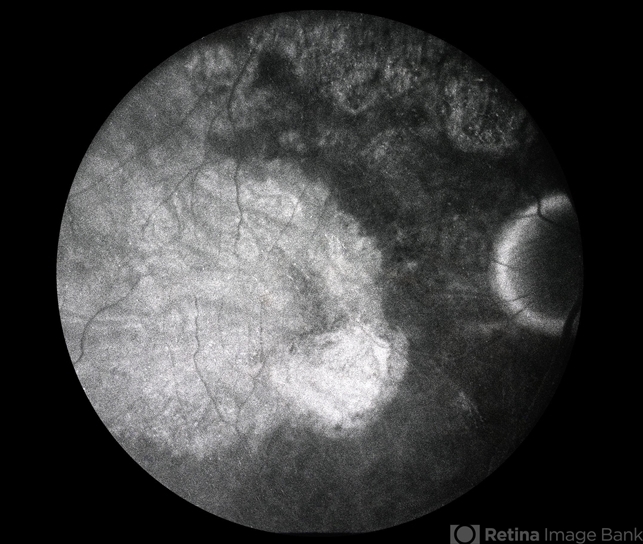

- subretinal hemorrhage, retinal pigment epithelium atrophy

- ARMD s/p surgical removal of massive subretinal hemorrhage, FA, with severe RPE atrophy.